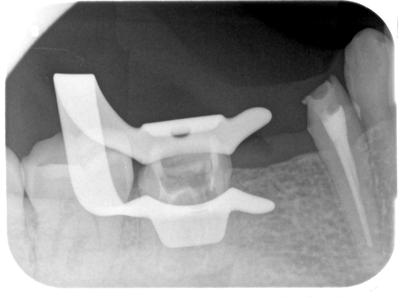

ブリッジを除去するとお粗末な根管治療、パーフォレーションなど、様々な問題。

2回に分け、概ね2時間かかって除去成功。

除去後写真、4┐は根管充填済

64┐根管充填後の写真

6┐、パーフォレーションも含め、オリジナルの根管を逸脱している可能性高かったためMTAにて根管充填。